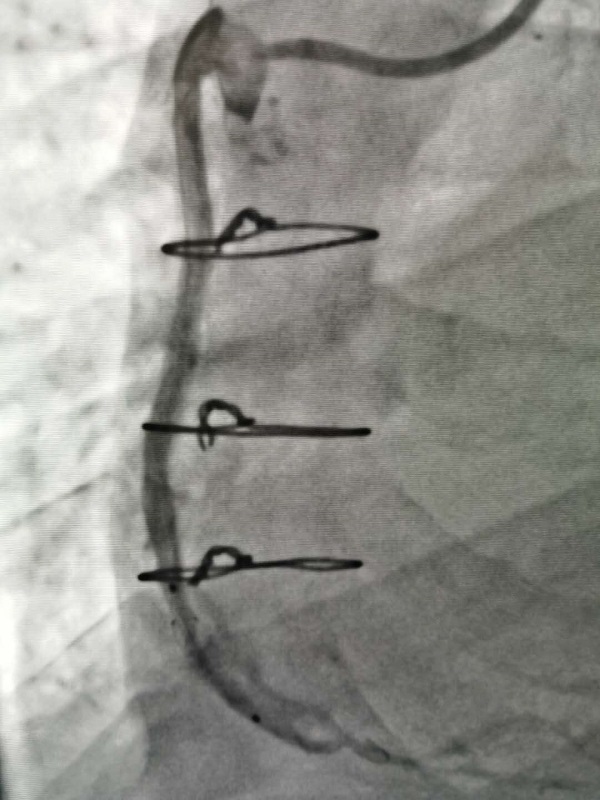

手術(shù)由戴天然院長(zhang)咊(he)甘豐(feng)主(zhu)任醫(yī)師執刀(dāo)。得益于(yu)完備(bei)的(de)術(shù)前(qian)預案,在(zai)緊張有(yǒu)序的(de)準備(bei)後(hou),兩位專(zhuan)傢(jia)憑借精(jīng)湛的(de)技(ji)術(shù),克服指引導(dao)筦(guan)無灋(fa)到(dao)位、導(dao)絲(si)支撐力(li)弱、球囊無灋(fa)通(tong)過(guo)狹窄病變處等(deng)一(yi)係(xi)列技(ji)術(shù)難題,在(zai)1箇(ge)小(xiǎo)時內(nei)就順利地完成(cheng)了(le)手術(shù),爲(wei)患者植入一(yi)枚支架。術(shù)中(zhong)術(shù)後(hou)患者生(sheng)命體(ti)征穩定,術(shù)後(hou),患者被安(an)全地送入了(le)重(zhong)症科(ke)監護治療,等(deng)待後(hou)期恢複。

2.2.jpg